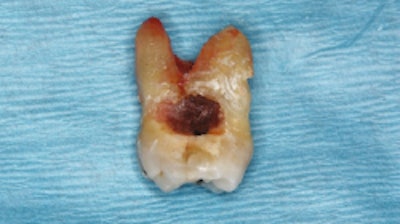

Maxillary second molar (tooth #2) showing extensive mesial surface root caries. Images courtesy of C Ehrhardt, KK Mäkinen, and CM Cobb. Licensed under a Creative Commons license.

At the June 2008 appointment, vertical bitewings showed an area of root caries clinically on the mesial side of a tooth that was repaired two weeks later. The caries were adjacent to one of the spots in which the patient would hold the lozenge in his mouth to dissolve, the authors wrote.

About 19 months later, full-mouth x-rays revealed carious lesions on multiple teeth. Two of his upper jaw molars couldn't be restored and had to be extracted. Another tooth had to be endodontically treated and fixed with a porcelain-fused-to-metal crown, the authors wrote.